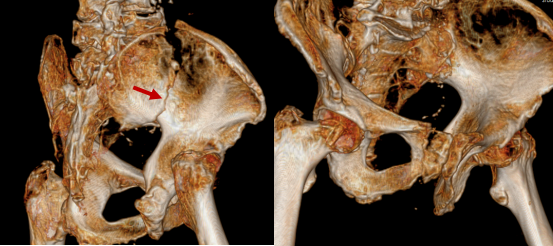

箭头所示病灶位置

然而病情并没有家属想象中简单,检查结果显示梁婆婆右侧耻骨上下支骨折、腰椎椎管狭窄,却未发现胸腰椎新鲜压缩骨折。经冯学烽主任、杨立进主治医师查体发现,婆婆还伴有臀、腿麻木症状。

手术由骨伤一科冯学烽主任与骨伤二科郭锋副主任联合主刀,先经2个小切口为骨盆置入3枚空心螺钉固定,再通过背部2个2.5cm小切口,完成腰椎减压、内固定及骨水泥加强操作,全程出血少、创伤小,减压效果显著。